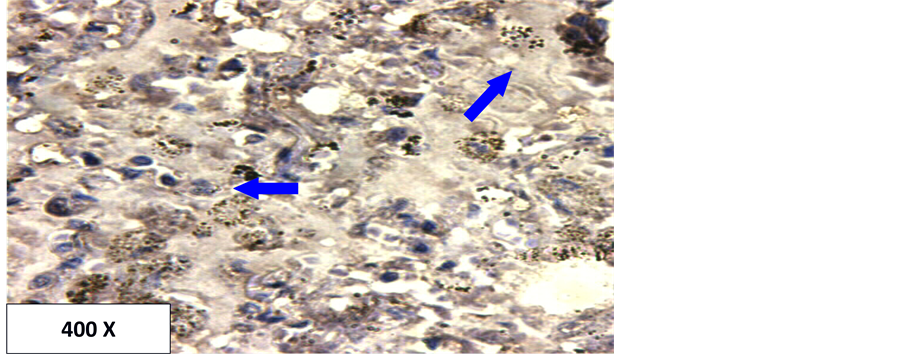

In the current study, the detection of p53 and Aspergillus antigen in lung tissues were investigated using immunohistochemistry technology. The results show that the Aspergillus is present in all used sample (100% of the infection) in the form of spores or hyphae (Table 1, Figures 1-3). It is also present within the blood vessels and within the interstitial spaces (Figure 2 and Figure 3). This high percent may be due to the highly specific and sensitive technique employed in this study (immunohistochemistry). Additionally, all cases in this study were from autopsy specimens, Autopsy specimens are more exposed to Aspergillus than other specimens. There may be relatively long time from death to obtain the specimens which may give a sufficient incubation time for the multiplication of Aspergillus.

Figure 1. Localization of Aspergillus spores in lung tissue using LSAB-Method. Brown color at the tip of the arrows indicates positive.